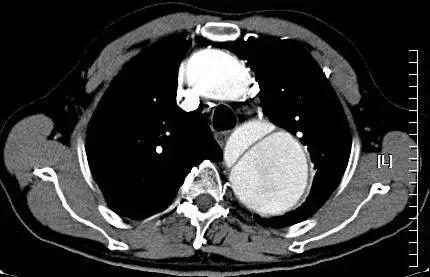

很快便完成了一系列的检查,果然同我心中的预测一样:主动脉夹层!

患者不仅是主动脉夹层,并且已经撕裂到腹主动脉!

而所谓主动脉夹层是由于血液通过动脉内膜破口进入主动脉壁中层形成夹层血肿,并且延伸剥离而引起的严重心血管急症。

我建议这位左上肢血压170/110 mmHg,右上肢血压160/90 mmHg的患者做胸部CT和腹部CT,必要时完善主动脉CTA检查,因为如果是这个死亡率极高的疾病,是需要尽早手术治疗的。